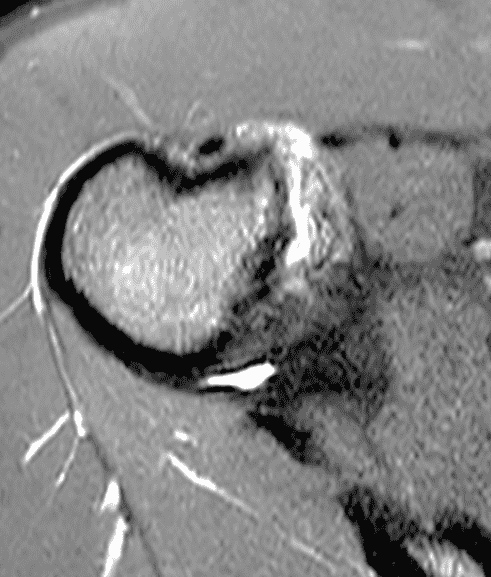

A 19 year old college baseball pitcher heard a “pop” after throwing a ball. Axial fat-suppressed proton density-weighted (1A and 1B), coronal fat-suppressed T2-weighted images (1C), and a Grashey projection radiograph (1D) images are provided. What are the findings? What is your diagnosis?

Figure 2: (2A) An axial image at the level of the humeral lesser tuberosity (LT) shows an intact subscapularis tendon (arrowheads). (2B) More inferiorly at the level of the humeral neck (HN), the direct muscular attachment of subscapularis (yellow arrows) is avulsed from the humerus together with the anterior band of the inferior glenohumeral ligament (red arrow), representing humeral avulsion of the glenohumeral ligament, a HAGL lesion. (2C) A coronal image through the anterior humerus shows the avulsed direct muscular attachment of subscapularis (yellow arrows), and the retracted end of the torn anterior band of the inferior glenohumeral ligament (red arrow). (2D) The radiograph shows a small, avulsed bone fragment of the humerus (red arrow), making this injury a “bony” HAGL (BHAGL) lesion. He failed 3 weeks of conservative management, with persistent 7/10 shoulder pain and was managed operatively with a lesser tuberosity repair. 6 months later, after taking a hiatus from baseball, his pain was completely resolved.